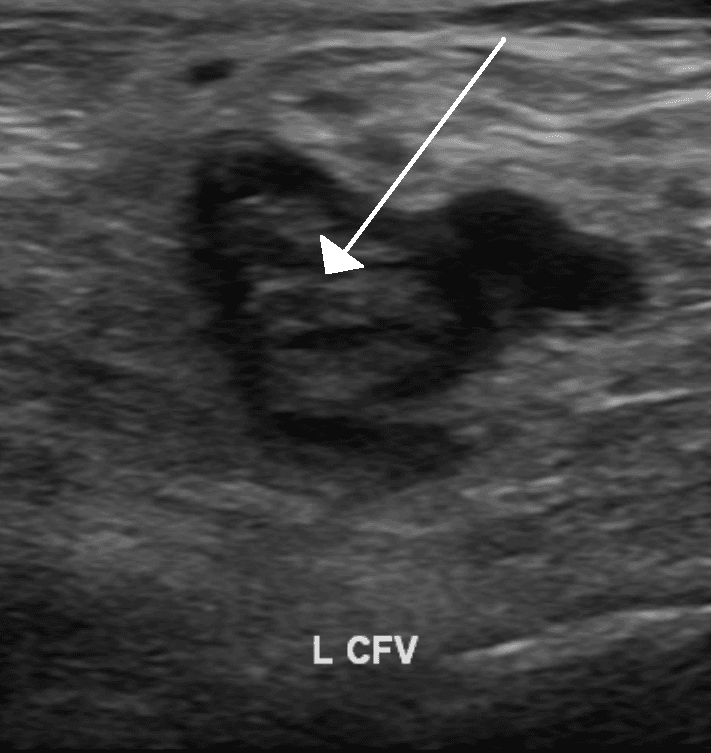

Thrombophilia (sometimes called hypercoagulability or a prothrombotic state) is an abnormality of blood coagulation that increases the risk of thrombosis (blood clots in blood vessels). Such abnormalities can be identified in 50% of people who have an episode of thrombosis (such as deep vein thrombosis in the leg) that was not provoked by other causes. A significant proportion of the population has a detectable thrombophilic abnormality, but most of these develop thrombosis only in the presence of an additional risk factor. There is no specific treatment for most thrombophilias, but recurrent episodes of thrombosis may be an indication for long-term preventive anticoagulation. The first major form of thrombophilia to be identified by medical science, antithrombin deficiency, was identified in 1965, while the most common abnormalities (including factor V Leiden) were described in the 1990s. The most common conditions associated with thrombophilia are deep vein thrombosis (DVT) and pulmonary embolism (PE), which are referred to collectively as venous thromboembolism (VTE). DVT usually occurs in the legs, and is characterized by pain, swelling and redness of the limb. It may lead to long-term swelling and heaviness due to damage to valves in the veins. The clot may also break off and migrate (embolize) to arteries in the lungs. Depending on the size and the location of the clot, this may lead to sudden-onset shortness of breath, chest pain, palpitations and may be complicated by collapse, shock and cardiac arrest. Venous thrombosis may also occur in more unusual places: in the veins of the brain, liver (portal vein thrombosis and hepatic vein thrombosis), mesenteric vein, kidney (renal vein thrombosis) and the veins of the arms. Whether thrombophilia also increases the risk of arterial thrombosis (which is the underlying cause of heart attacks and strokes) is less well established. However, more recent data suggest some forms of inherited thrombophilia are associated with increased risk for arterial ischemic stroke.